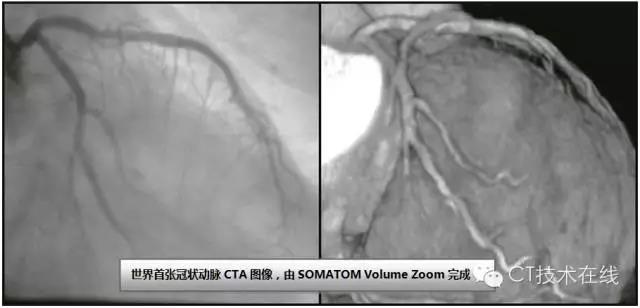

1998年西门子在RSNA年会推出首台多层CT SOMATOM Volume Zoom,能在0.5 s/周内获得4个图像断面,其后又以16层、64层及128层CT领跑多层CT的发展。

SOMATONM Volume Zoom的问世解决了扫描范围和精确细节之间的矛盾,尤其重要的是,SOMATOM Volume Zoom也是心脏CT扫描史上的重要转折点。

首张冠状动脉CT图像于1999年在德国慕尼黑Klinikum Grosshadern医院诞生。

在此后几年里,西门子在心脏成像领域内作出了重大贡献——如果没有西门子,如今的心脏CT将不可能成为一项临床常规检查。